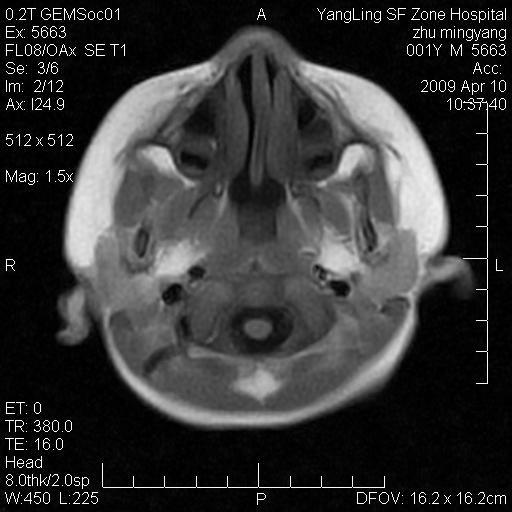

患者:1岁半,两天前外伤收住我院,ct检查小脑占位

考虑星形细胞瘤,建议增强

髓母细胞瘤或血管母细胞瘤,增强后可以鉴别;影像资料见 <。鱼博浪老师的《中枢神经系统ct与mr鉴别诊断》 小脑部肿瘤章节。

髓母细胞瘤或血管母细胞瘤!支持!

支持考虑髓母细胞瘤

考虑----髓母细胞瘤可能性大

考虑髓母细胞瘤或室管膜瘤。

支持髓母细胞瘤。

考虑髓母细胞瘤。

考虑髓母细胞瘤或星形细胞瘤

考虑髓母细胞瘤.

考虑髓母细胞瘤可能性大。

小脑肿瘤.考虑髓母细胞瘤可能.

就病灶部位及临床资料首先考虑髓母.